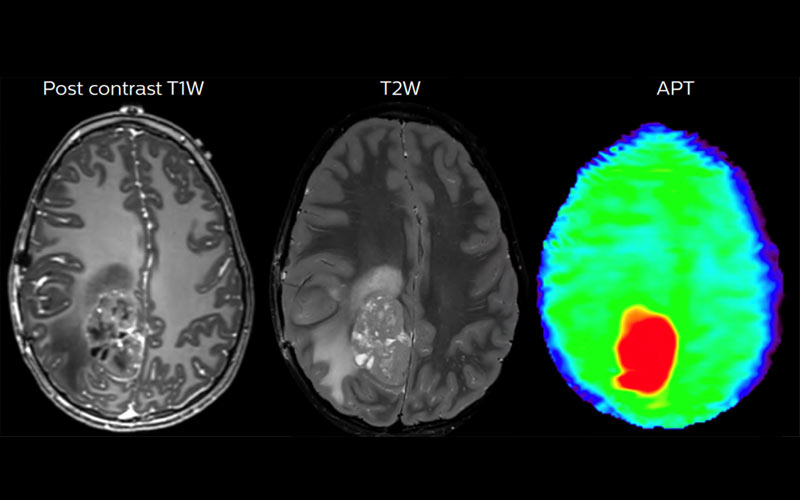

:quality(85)/cloudfront-us-east-1.images.arcpublishing.com/infobae/UAPMDGOOERGQ3I3FAMV6T6HZXQ.jpg%20420w) Pero algunas personas presentan resistencia a las inmunoterapias y otros tienen tumores calificados como “inmunológicamente fríos”, ya que evaden o suprimen la respuesta inmunitaria del paciente contra su cáncer

Pero algunas personas presentan resistencia a las inmunoterapias y otros tienen tumores calificados como “inmunológicamente fríos”, ya que evaden o suprimen la respuesta inmunitaria del paciente contra su cáncerLos especialistas consideran que las inmunoterapias de cáncer han revolucionado los tratamientos contra el cáncer porque potencia al sistema inmunitario de los pacientes a combatir los tumores. Pero algunas personas presentan resistencia a las inmunoterapias y otros tienen tumores calificados como “inmunológicamente fríos”, ya que evaden o suprimen la respuesta inmunitaria del paciente contra su cáncer.

Para este tipo de pacientes, los médicos ya están aplicando una radioterapia de haz externo, conocida por su sigla EBRT, en la que se coloca al paciente en una máquina que dirige la radiación directamente al tumor y, en muchos casos, logran así convertir esos tumores “fríos” o resistentes, en “calientes” de forma tal que las inmunoterapias son más efectivas.

Pero las terapias EBRT no están indicadas para pacientes con metástasis, es decir, que con cáncer que se ha extendido a otras partes del cuerpo. Así, la EBRT no actúa ante la presencia de tumores distantes ya que podría generar que el paciente no tolere tanta radiación. Aquí, los médicos, en ocasiones, evalúan correcto usar una terapia con radionúclidos dirigida.